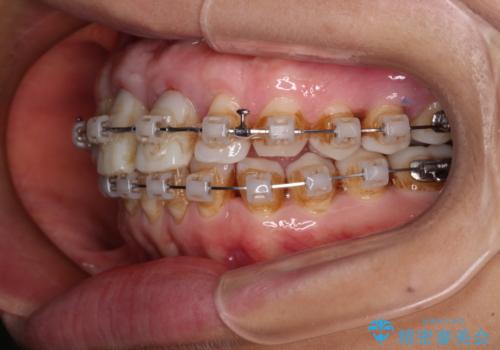

- 矯正装置

- クリアブラケット

- 治療期間

- 2年6ヶ月

- 治療回数

- 30回以上